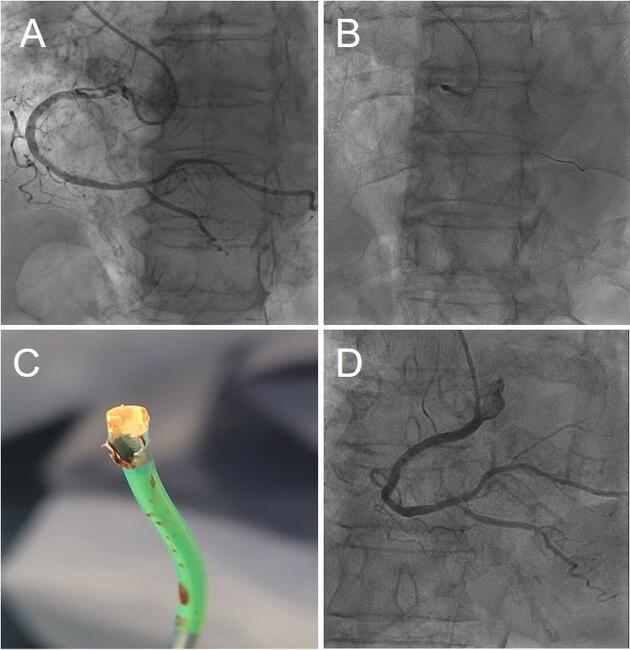

Video 2. The 1.75-mm burr exiting the 6F Launcher Amplatz Left guide (Medtronic), illustrating the extreme spatial constraint within the distal curve.

Video 3. Stent delivery using a double-wire (aorta/right coronary artery) technique; retrospective analysis showed deformation of the guide catheter tip.